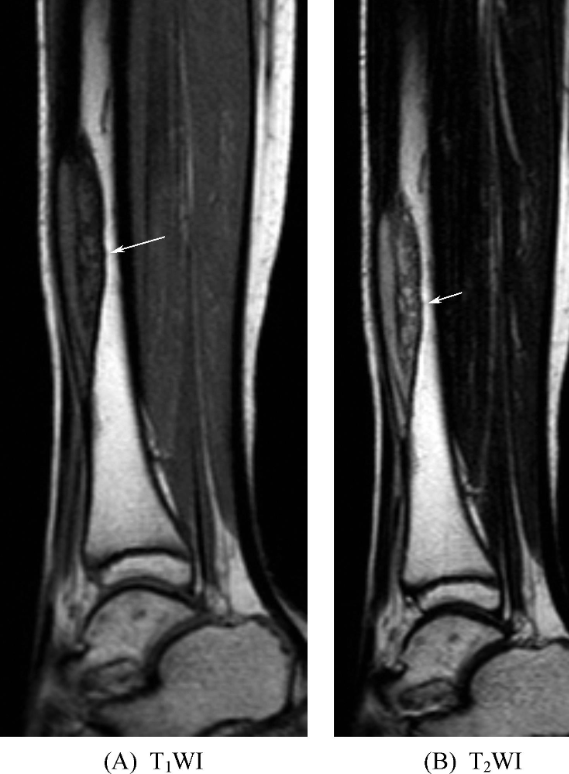

骨纤维异常增生症可发生于单骨、单肢、单侧或多骨多发。单骨型多见,好发于四肢骨;躯干骨以多骨型常见。发生于四肢管状骨者病变多始于干骺端或骨干并逐渐扩展,较少累及骨骺。发生于颅骨者常多骨受累。病变形态多样,T1WI上多为低信号,T2WI依含骨小梁、细胞、胶原、囊变及出血等成分的不同,可以是高信号也可以是低信号(图9)。可并发骨骼畸形和病理性骨折。

图9 骨纤维异常增生症胫骨中下段局部膨胀,可见一纵向走行的梭形肿块影,T1WI呈不均匀低信号,T2WI呈不均匀高信号,边界清晰,可见低信号硬化缘。